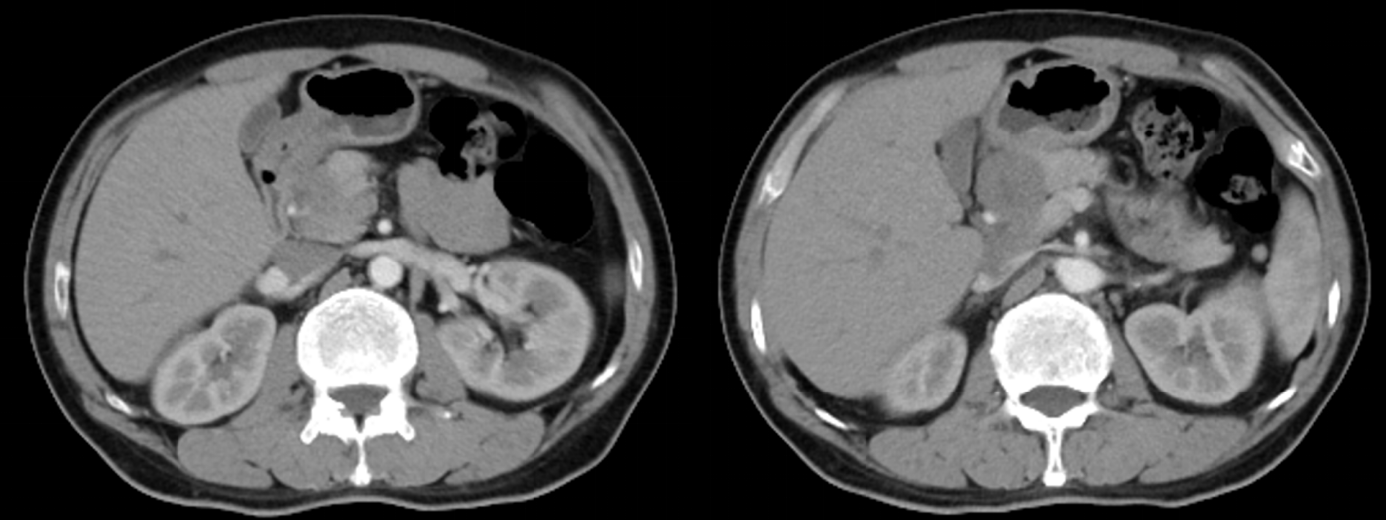

2023-10-27于当地医院行腹盆CT:胃窦壁增厚,肝胃间隙、肝门区及大网膜区见肿大淋巴结,大者最大截面约3.9*2.7cm,腹膜后可见稍大淋巴结(图1)。

2024-03-12腹盆CT回报:对比2024-01-19腹盆CT:胃窦部胃壁增厚减轻,较厚处原约12mm,现约9mm,与正常胃壁分界不清,浆膜面模糊。No.1-3,7-8,9组多发淋巴结,部分增大,较大原约34*31mm,现约46*31mm,与胰腺分界欠清(图2)。临床疗效评价:综合考虑PD。